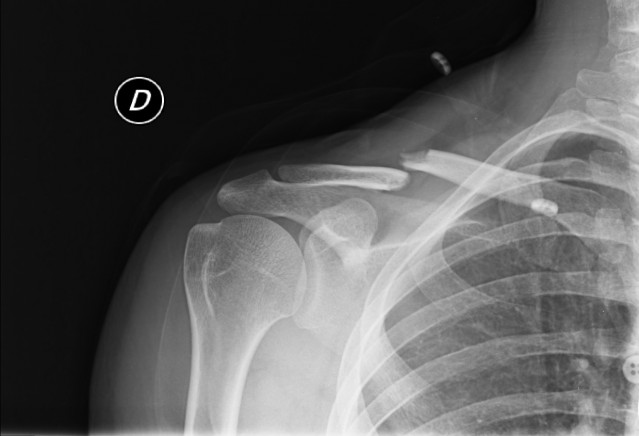

La ferraglia non me la toglie, conferma il fatto che è di letale importanza per me!!